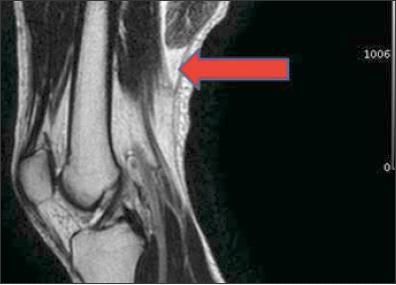

Figure 2 –

Shown here on a T2-weighted MRI scan is a complete tear of the distal end of the long head of the biceps femoris (arrow) with retraction.

MRI may be a more sensitive measure because of sonographer experience. It may be helpful if the diagnosis is unclear, if physical examination findings are out of proportion to the mechanism of injury or objective findings, or if it is important to quantify injury severity in a high-level athlete (Figures 2 and 3). Hematoma and interstitial edema are well visualized on T2- weighted images. MRI also may be helpful in the evaluation of complete tears with tendon retraction for surgical decision making.